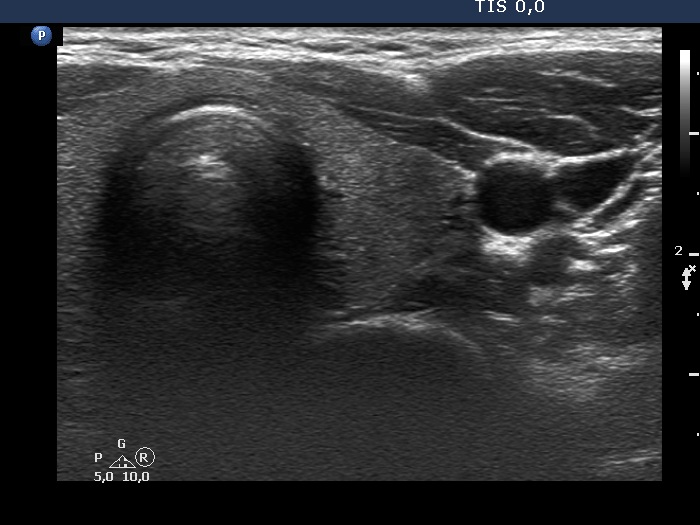

Initial examination (first row of images):

Clinical presentation: A 33-year-old woman was referred for evaluation of complaints suggesting hypothyroidism, including 12 kg weight gain, fatigue.

Palpation: Both lobes were palpable and not firm.

Laboratory examination: TSH 0.79 mIU/L, anti-TPO < 28 IU/mL.

Ultrasonography: The thyroid was echonormal and intact.